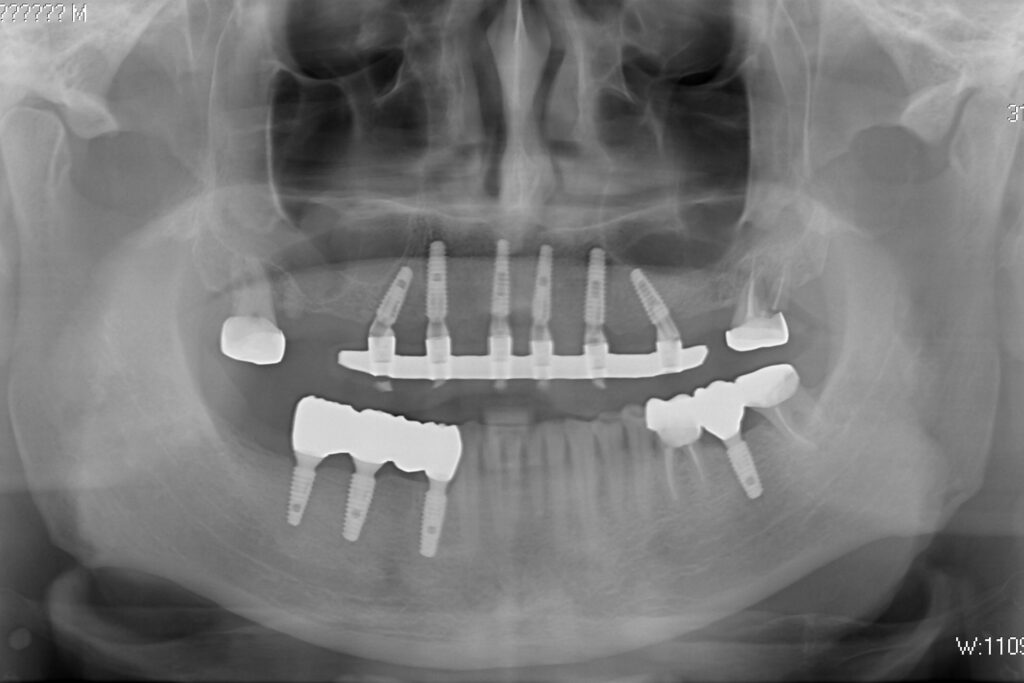

Пациенту были установлены 6 имплантатов Megagen AnyOne по системе All-on-6 на верхней челюсти и 4 имплантата на нижней по классической двухэтапной методике.

Спустя 27 дней был зафиксирован протез с опопрой на дентальные имплантаты из диоксида циркония с каркасом из титана.

Также на нижнюю челюсть был изготовлен мостовидный протез из 4х коронок (цирконий) с опорой на 3 индивидуальных абатмента с одной стороны и 1 коронка на иплантат с другой.